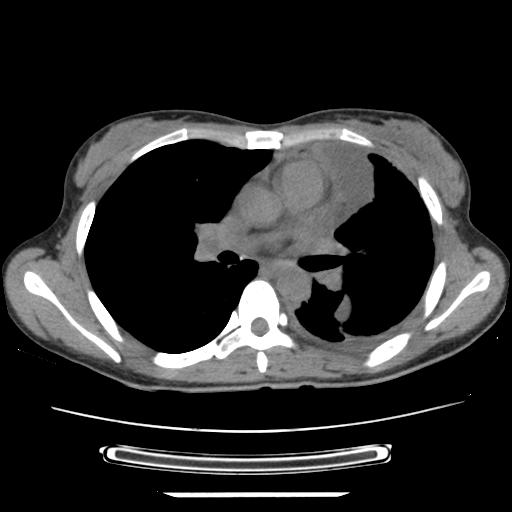

标题: CT21561:外院胸片提示胸腔积液,行CT检查。 [打印本页]

女,29岁,胸部不适,在外院胸片提示胸腔积液,到我院ct检查。

纵膈窗

1、左侧包裹性积液伴叶间积液 2、右肺多发结节考虑增殖结节

左侧纵隔胸膜包裹性积液、左侧胸腔积液、胸膜肥厚粘莲,考虑结核性胸膜炎

左肺上叶不张,左侧胸水,叶间裂积液,纵隔淋巴结,脾脏钙化,考虑左肺上叶支气管内膜结核,结核性胸膜炎,脾结核

考虑:1.两肺tb;2.左侧胸膜炎、胸腔积液。

考虑两肺结核,左侧包裹性积液,叶间积液。

支持两肺继发性肺结核,左侧胸膜腔包裹性积液、胸膜肥厚,脾内多发钙化(结核钙化)。

右肺多发结节。左胸腔多发包裹性积液。